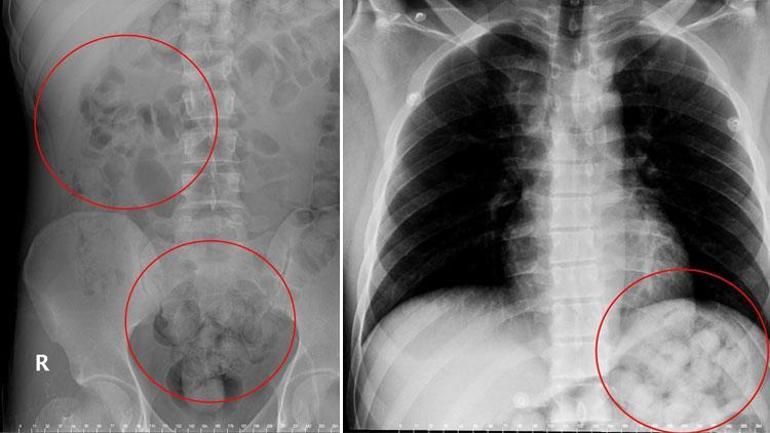

Van’dan İstanbul’a giden bir yolcu otobüsünde seyahat eden yabancı uyruklu Zadeh Ahmed Narziveh, araç Ankara şehirlerarası otobüs terminali AŞTİ’ye vardığında fenelaştı. Durumunun bildirilmesi üzerine gelen 112 Acil Servis ekiplerince ilk müdahalesi yapılan Narziveh, ardından ambulans ile şehir hastanesine kaldırıldı. Narziveh’in, hastanede çekilen röntgeninde midesinde uyuşturucu kapsülleri görülünce Narkotik polis ekiplerine bilgi verildi. Hastaneye gelen Narkotim ekiplerinin gözetiminde ameliyata alınan Narziveh’in midesinde 2’si patlamış, 72 kapsül halinde 890 gram uyuşturucu madde metamfetamin çıkarıldı.

Narkotim ekiplerinin gözetiminde 5 gün hastanede tedavi gören Narziveh, iyileşince hastaneden taburcu edildikten sonra, gözaltına alınarak emniyete götürüldü. Yapılan sorgusunda “susma” hakkını kullanan Narziveh, ifade vermedi. Narkotim ekipleri, Narziveh’in bağlantılarını belirlemek, uyuşturucuyu kimden aldığı, nereye götürdüğünü ortaya çıkarmak için çalışma başlattı. Yapılan incelemelerde Narziveh’in İstanbul’dan Van’a gittiği, burada İran üzerinden Türkiye’ye sokulan uyuşturucu kapsüllerini yuttuğu belirlendi. Narziveh’in, midesindeki 1 kiloya yakın uyuşturucuyla Van’dan otobüse binerek İstanbul’a gitmek için yola çıktığı kaydedildi.